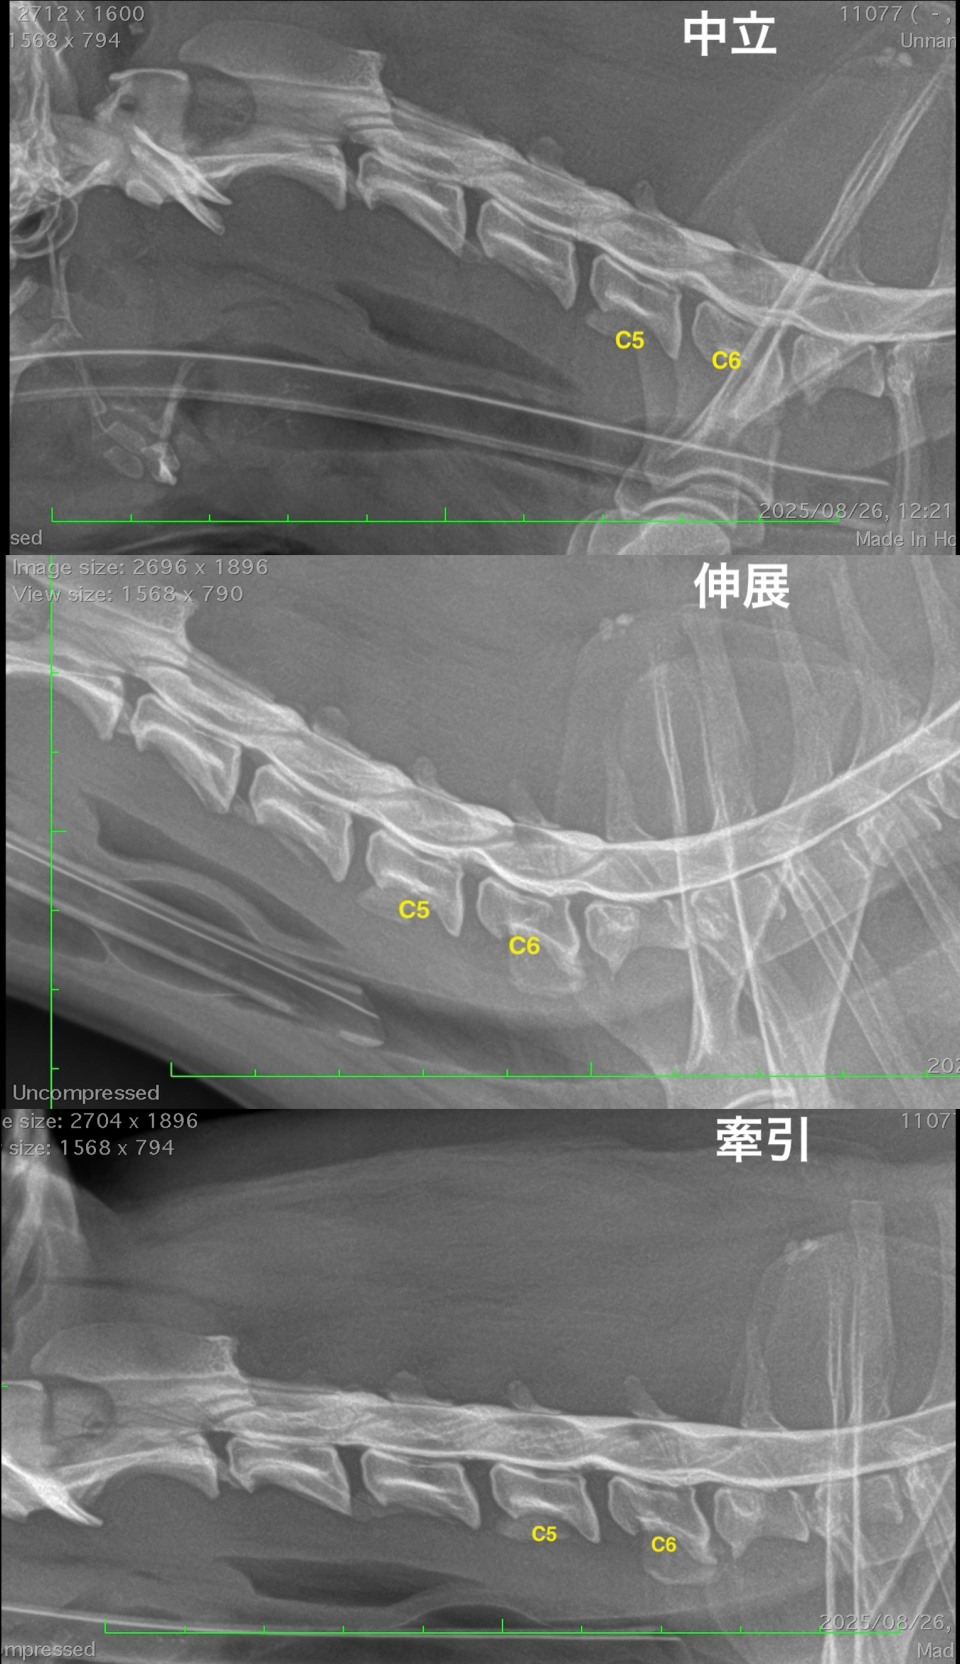

責任病変の特定と椎間板関連動的圧迫の検出のための脊髄造影検査/脊髄造影ダイナミック検査を実施したところ、C5-6椎間において伸展時に圧迫の程度が悪化し、牽引時に軽減する脊髄動的圧迫所見が認められました。

MRI検査のみでは多発性椎間板ヘルニアにおける責任病変の特定が困難な場合があり、脊髄動的圧迫は評価できません。

本症例は脊髄造影検査および脊髄造影ダイナミック検査を実施することで、C5-6椎間の椎間板ヘルニアおよび脊椎不安定症と診断することができました。